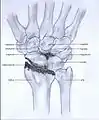

Stages

Post-traumatic osteoarthritis can be classified into four stages.[1][7] These stages are similar between SLAC and SNAC wrists. Each stage has a different treatment.

- Stage I: the osteoarthritis is only localized in the distal scaphoid and radial styloid.

- Stage II: the osteoarthritis is localized in the entire radioscaphoid joint.

- Stage III: the osteoarthritis is localized in the entire radioscaphoid joint with involvement of the capitolunate joint.

- Stage IV: the osteoarthritis is located in the entire radiocarpal joint and in the intercarpal joints. It also may involve the distal radio-ulnar joint (DRUJ).

Stage I

Stage II